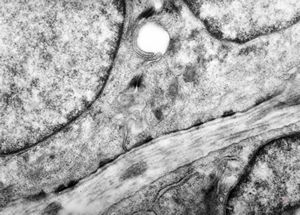

M, 48y. | multiplication of dermal perivascular basement membranes (unclassified myopathy)